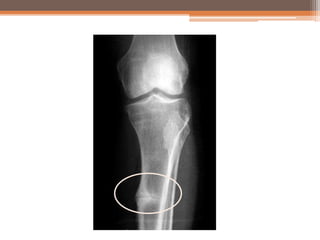

Looser’s Zone

• #16 http://radiopaedia.org/cases/loosers-zones-osteomalacia